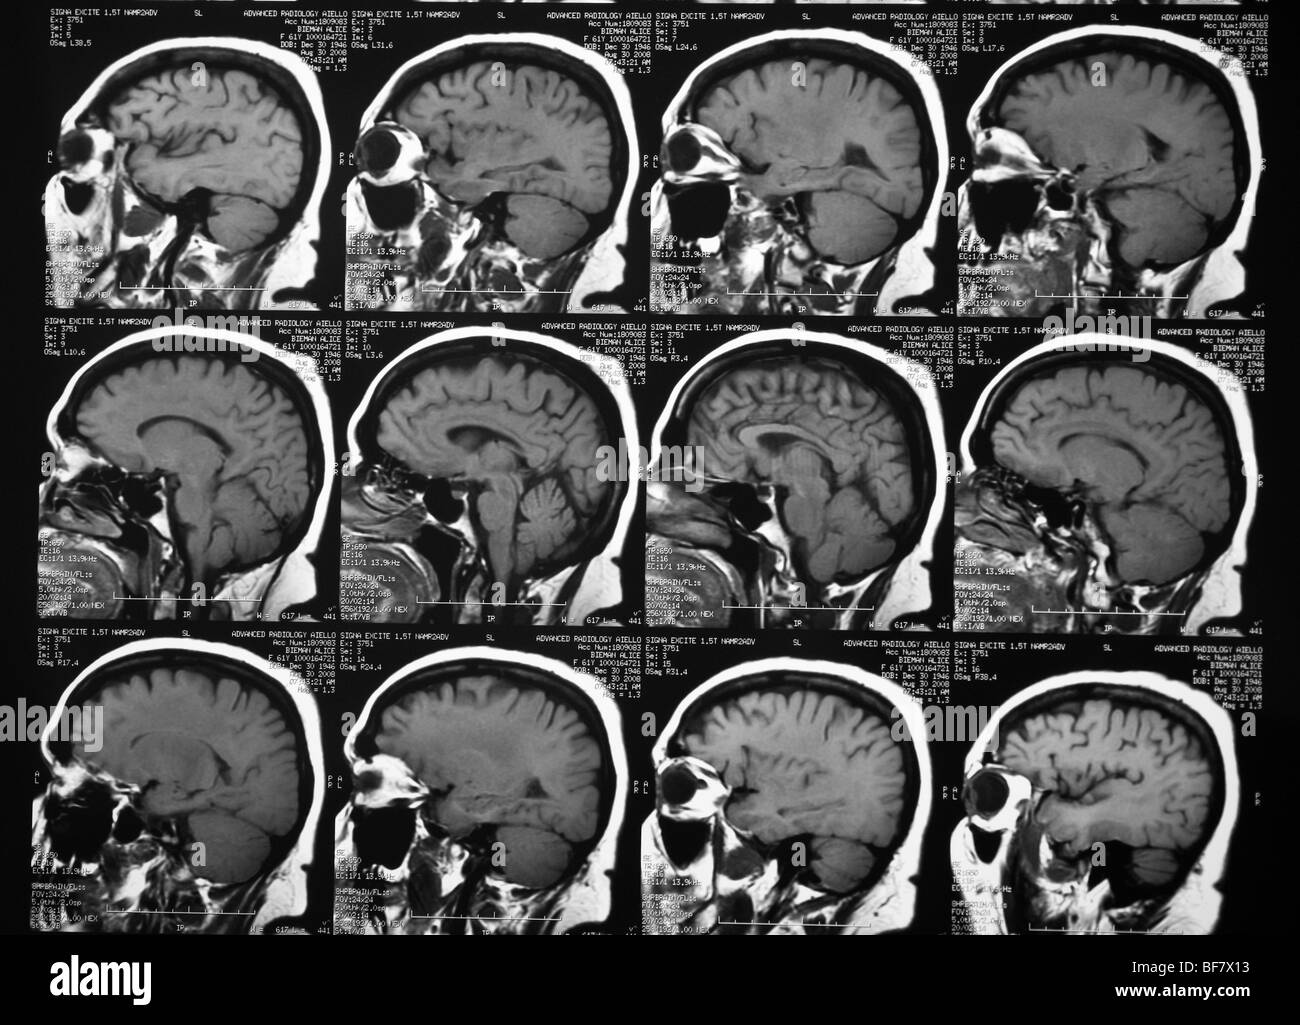

La tomodensitométrie de la tête humaine Banque D'Imageshttps://www.alamyimages.fr/image-license-details/?v=1https://www.alamyimages.fr/photo-image-la-tomodensitometrie-de-la-tete-humaine-26604287.html

La tomodensitométrie de la tête humaine Banque D'Imageshttps://www.alamyimages.fr/image-license-details/?v=1https://www.alamyimages.fr/photo-image-la-tomodensitometrie-de-la-tete-humaine-26604287.htmlRMBF7X13–La tomodensitométrie de la tête humaine